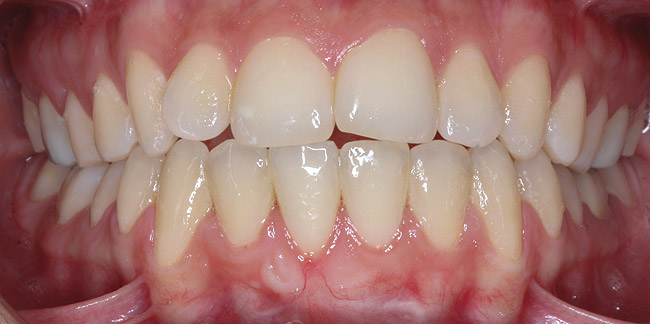

CASE 6 Fig 14. Post-orthodontic Miller Class II recession treated with a combined orthodontic-surgical approach. Clinical view 5 years after first orthodontic treatment showing GR of right lower incisor and a labially prominent root.

Figure 14

Fig 15. Same patient 2 years later showing worsening of GR and inflammation.

Figure 15